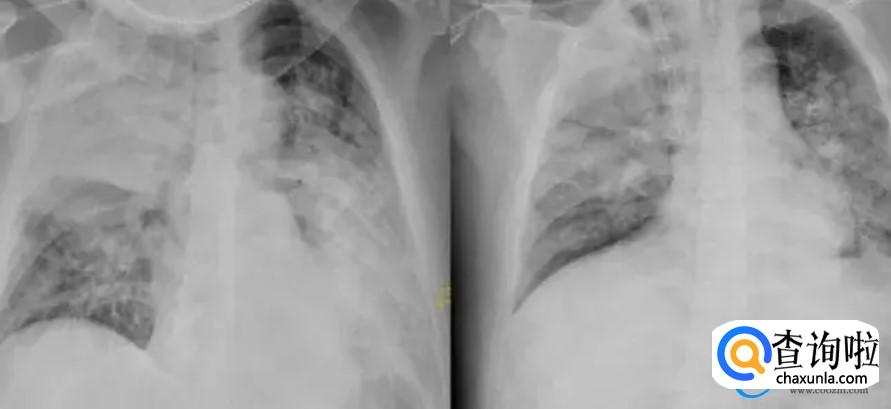

很多患者感染新冠之后,可能会对肺部造成一定的影响,这些相对来说情况是比较轻微的。通过肺部的CT检查时,要是发现肺部已经出现了毛玻璃样的东西,此时代表肺部已经有炎症,情节较为严重的时候会直接出现白肺纤维化,最后导致呼吸衰竭而亡。

近期众人对白肺的关注度较高,白肺主要是指肺内部出现了病变,从而导致肺部的透亮度开始大幅度的降低。一旦出现白肺之后,可能会形成非常严重的肺部感染,要是毒性肺炎或者是细菌性肺炎,导致白肺形成之后,可能会直接出现急性呼吸窘迫的症状。

目前白肺所表现的临床症状主要是呼吸困难、咳嗽喘憋等等症状,感染的时候比较明显,要是出现体温升高,此时需要及时的去医院拍CT检查。